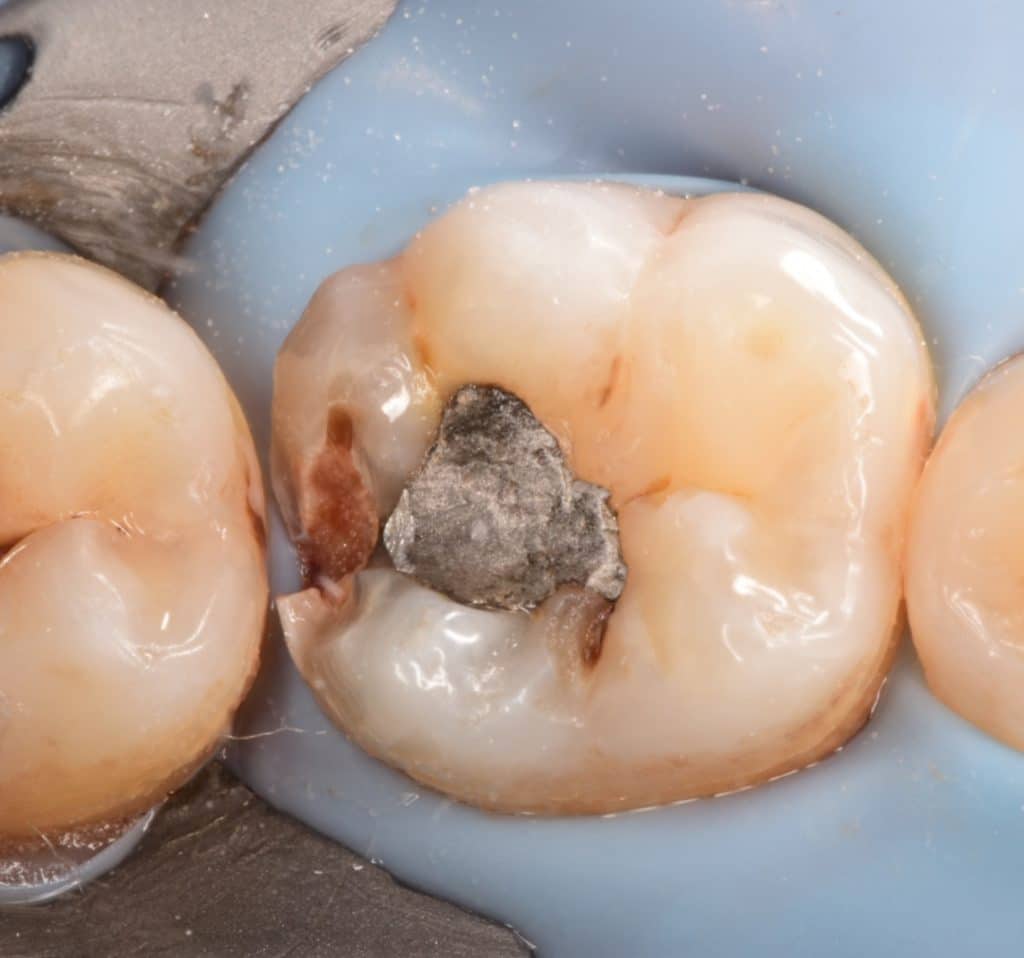

Initial situation showing badly restored lower first molar with amalgam filling

_old amalgam removed from first molar that’s causes a large and deep cavity even from the old and small previous amalgam filling.

Buccal view showing the depth of the cavity of the #6 and slo the mesail wall of the second molar with Initial caries need to prepared